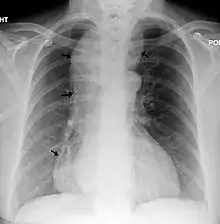

| Chest x-ray of an individual with achalasia. The arrows point to the areas of extreme esophageal dilation. | |